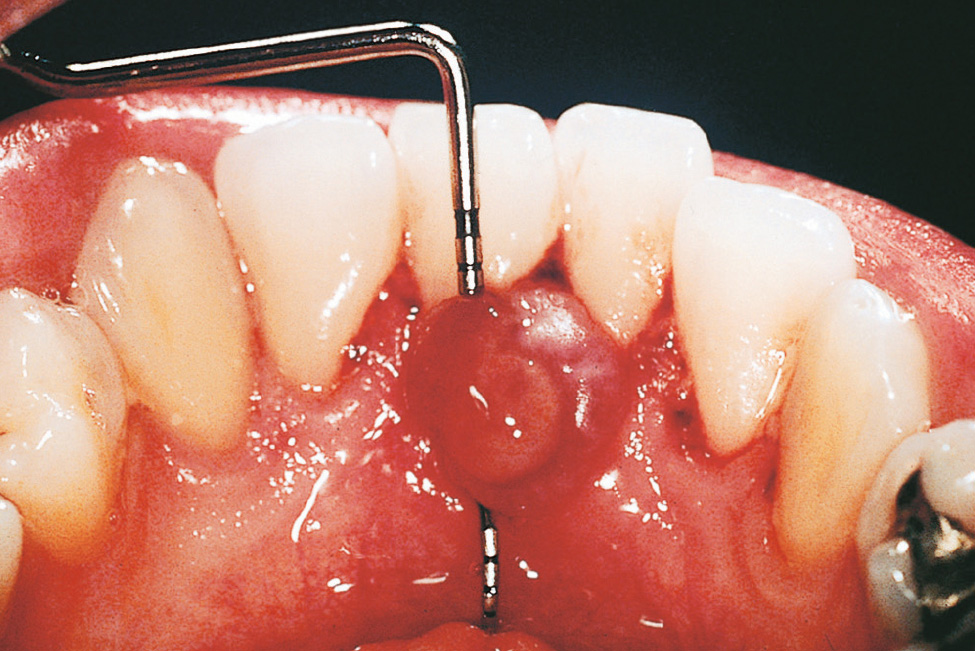

Lokalisierte, exophytische Wucherungen der marginalen Gingiva entstehen bevorzugt im Frontzahnbereich. Sie werden als Epulis vascularis (pyogenes Granulom)3 oder als „Schwangerschaftstumor“ (auch Epulis gravidarum) bezeichnet (Abb. 2). Zu dieser Veränderung kommt es infolge kleiner Gewebstraumen als übermäßige entzündliche Entwicklung von Granulationsgewebe. Vaskuläre Epuliden treten aber nicht nur im Rahmen einer Schwangerschaft auf und können neben einer gingivalen Lokalisation auch an der Zunge, Lippe, der Wangenschleimhaut, dem Gaumen, dem Vestibulum und an Frenula beobachtet werden.

Abb. 2 Pyogenes Granulom, das während der Schwangerschaft auftrat.

Die Epulis vascularis ist eine zumeist interdental gestielte, im Vergleich zu anderen Wucherungen streng lokalisierte Gewebevergrößerung, die innerhalb weniger Monate ihre volle Größe entwickelt (meist < 20 mm)4. Die Oberfläche des Granuloms ist rötlich und häufig ulzeriert bzw. fibrinbedeckt, und sie neigt stark zu Spontanblutungen. Die Inzidenz für eine Epulis vascularis während der Schwangerschaft wird mit 0,5 bis 5 % angegeben5. Eine operative Entfernung ist nur sinnvoll, wenn es durch das Granulom zu Störungen beim Essen oder Sprechen kommt. Ansonsten bildet sich sowohl die lokalisierte als auch die generalisierte Gingivawucherung nach der Geburt auch ohne chirurgische Intervention zumeist zurück.